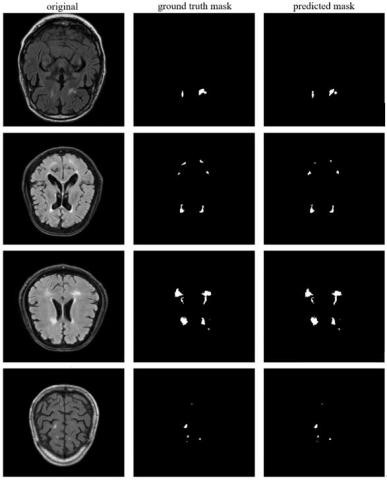

In the experimental studies carried out using the U-Net on the WMH dataset, 0.82 segmentation score on pixel basis was achieved for DSC. In addition, 0.83, 0.83 and 0.82 scores were obtained for PRC, RC and F1, respectively. The results of some segmented images on WMH dataset with U-Net are shown in Figure 13. Here, original MR images (a, b, c, d), expert-marked stroke lesion area (ground truth), and semantic segmentation masking of U-Net detected lesion areas are presented.

Figure 13. Some segmented MR images with U-Net technique in WMH Segmentation Challenge dataset

Some images of successful WMH segmentation with Mask R-CNN deep learning technique in WMH Segmentation Challenge dataset are shown in Figure 14. Here, the original MR image for four different MR images, WMH region (ground truth) masks marked by the expert, WMH region segmented with Mask R-CNN (predicted mask), over-lapping of Mask R-CNN segmentation and ground truth (predicted seg.), zoomed-in view of the WMH segmentation result are shown.

Figure 14. Some segmented MR images with Mask R-CNN technique in WMH Segmentation Challenge dataset